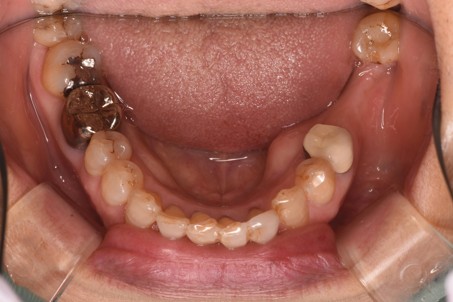

治療後 ![]() |

使い始めは違和感があったみたいですが、入れ歯にも慣れていただき現在は快適に咬めているとのことでした。 |